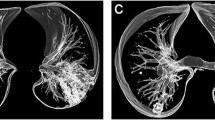

QCT was carried out on all CT scans. FACT-Digital lung TM software (DeXin, Xi'an, China) was used to perform fully automated three-dimensional CT quantitative measurements. The steps of segmentation were briefly undertaken as follows: (1) segmentation of the whole lung: a well-established thresholding operation was used to extract the lung volume. The threshold is determined based on intensity histogram analysis of the CT images; (2) segmentation of abnormal opacity: it was conducted by means of a 3D region-growing algorithm and a histogram-based thresholding technique; (3) bronchus and pulmonary vessels were segmented: a differential geometric approach was applied to automatically segment the vascular tree and airway tree. A “puzzle game” procedure acting as a “correction” operation for filtering false identifications was utilized; (4) quantitative evaluation of lesion’s volume was conducted after segmentation. The quantitative parameters included the lung volume (LV), total lesion volume (TLV), and percentage of abnormal opacity volume (lesion%). The pixels in abnormal opacity were processed with histogram analysis including an illustration of pixel attenuation (CT numbers). Histogram analysis also allowed measurements of mean density (MD) and the proportion of pixels related to ground-glass opacity (GGO). The details of the algorithm used in the software have been reported in previous studies ([12,13,14,15]; see Fig. 1).

The QCT could herein automatically segment and identify lung volume, bronchus, small pulmonary vessels, and abnormal opacity. It is a three-dimensional (3D) non-projection technique possessing a number of advantages to other densitometry techniques including high accuracy in segmentation, and easiness of operation. This approach was reported in our previous publication, and proven ability to segment accurately.